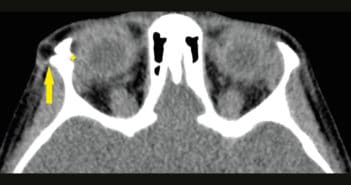

Quand les cellules visuelles ont disparu, on pourra imaginer l’utilisation de cellules souches rétiniennes en cours de développement mais, pour l’instant, la seule alternative aux stades terminaux est l’utilisation de photorécepteurs artificiels quand il n’y a plus aucune vision centrale. Tous les patients devraient bénéficier d’une rééducation basse vision dès qu’une gêne est notée, améliorant souvent la qualité de vie.